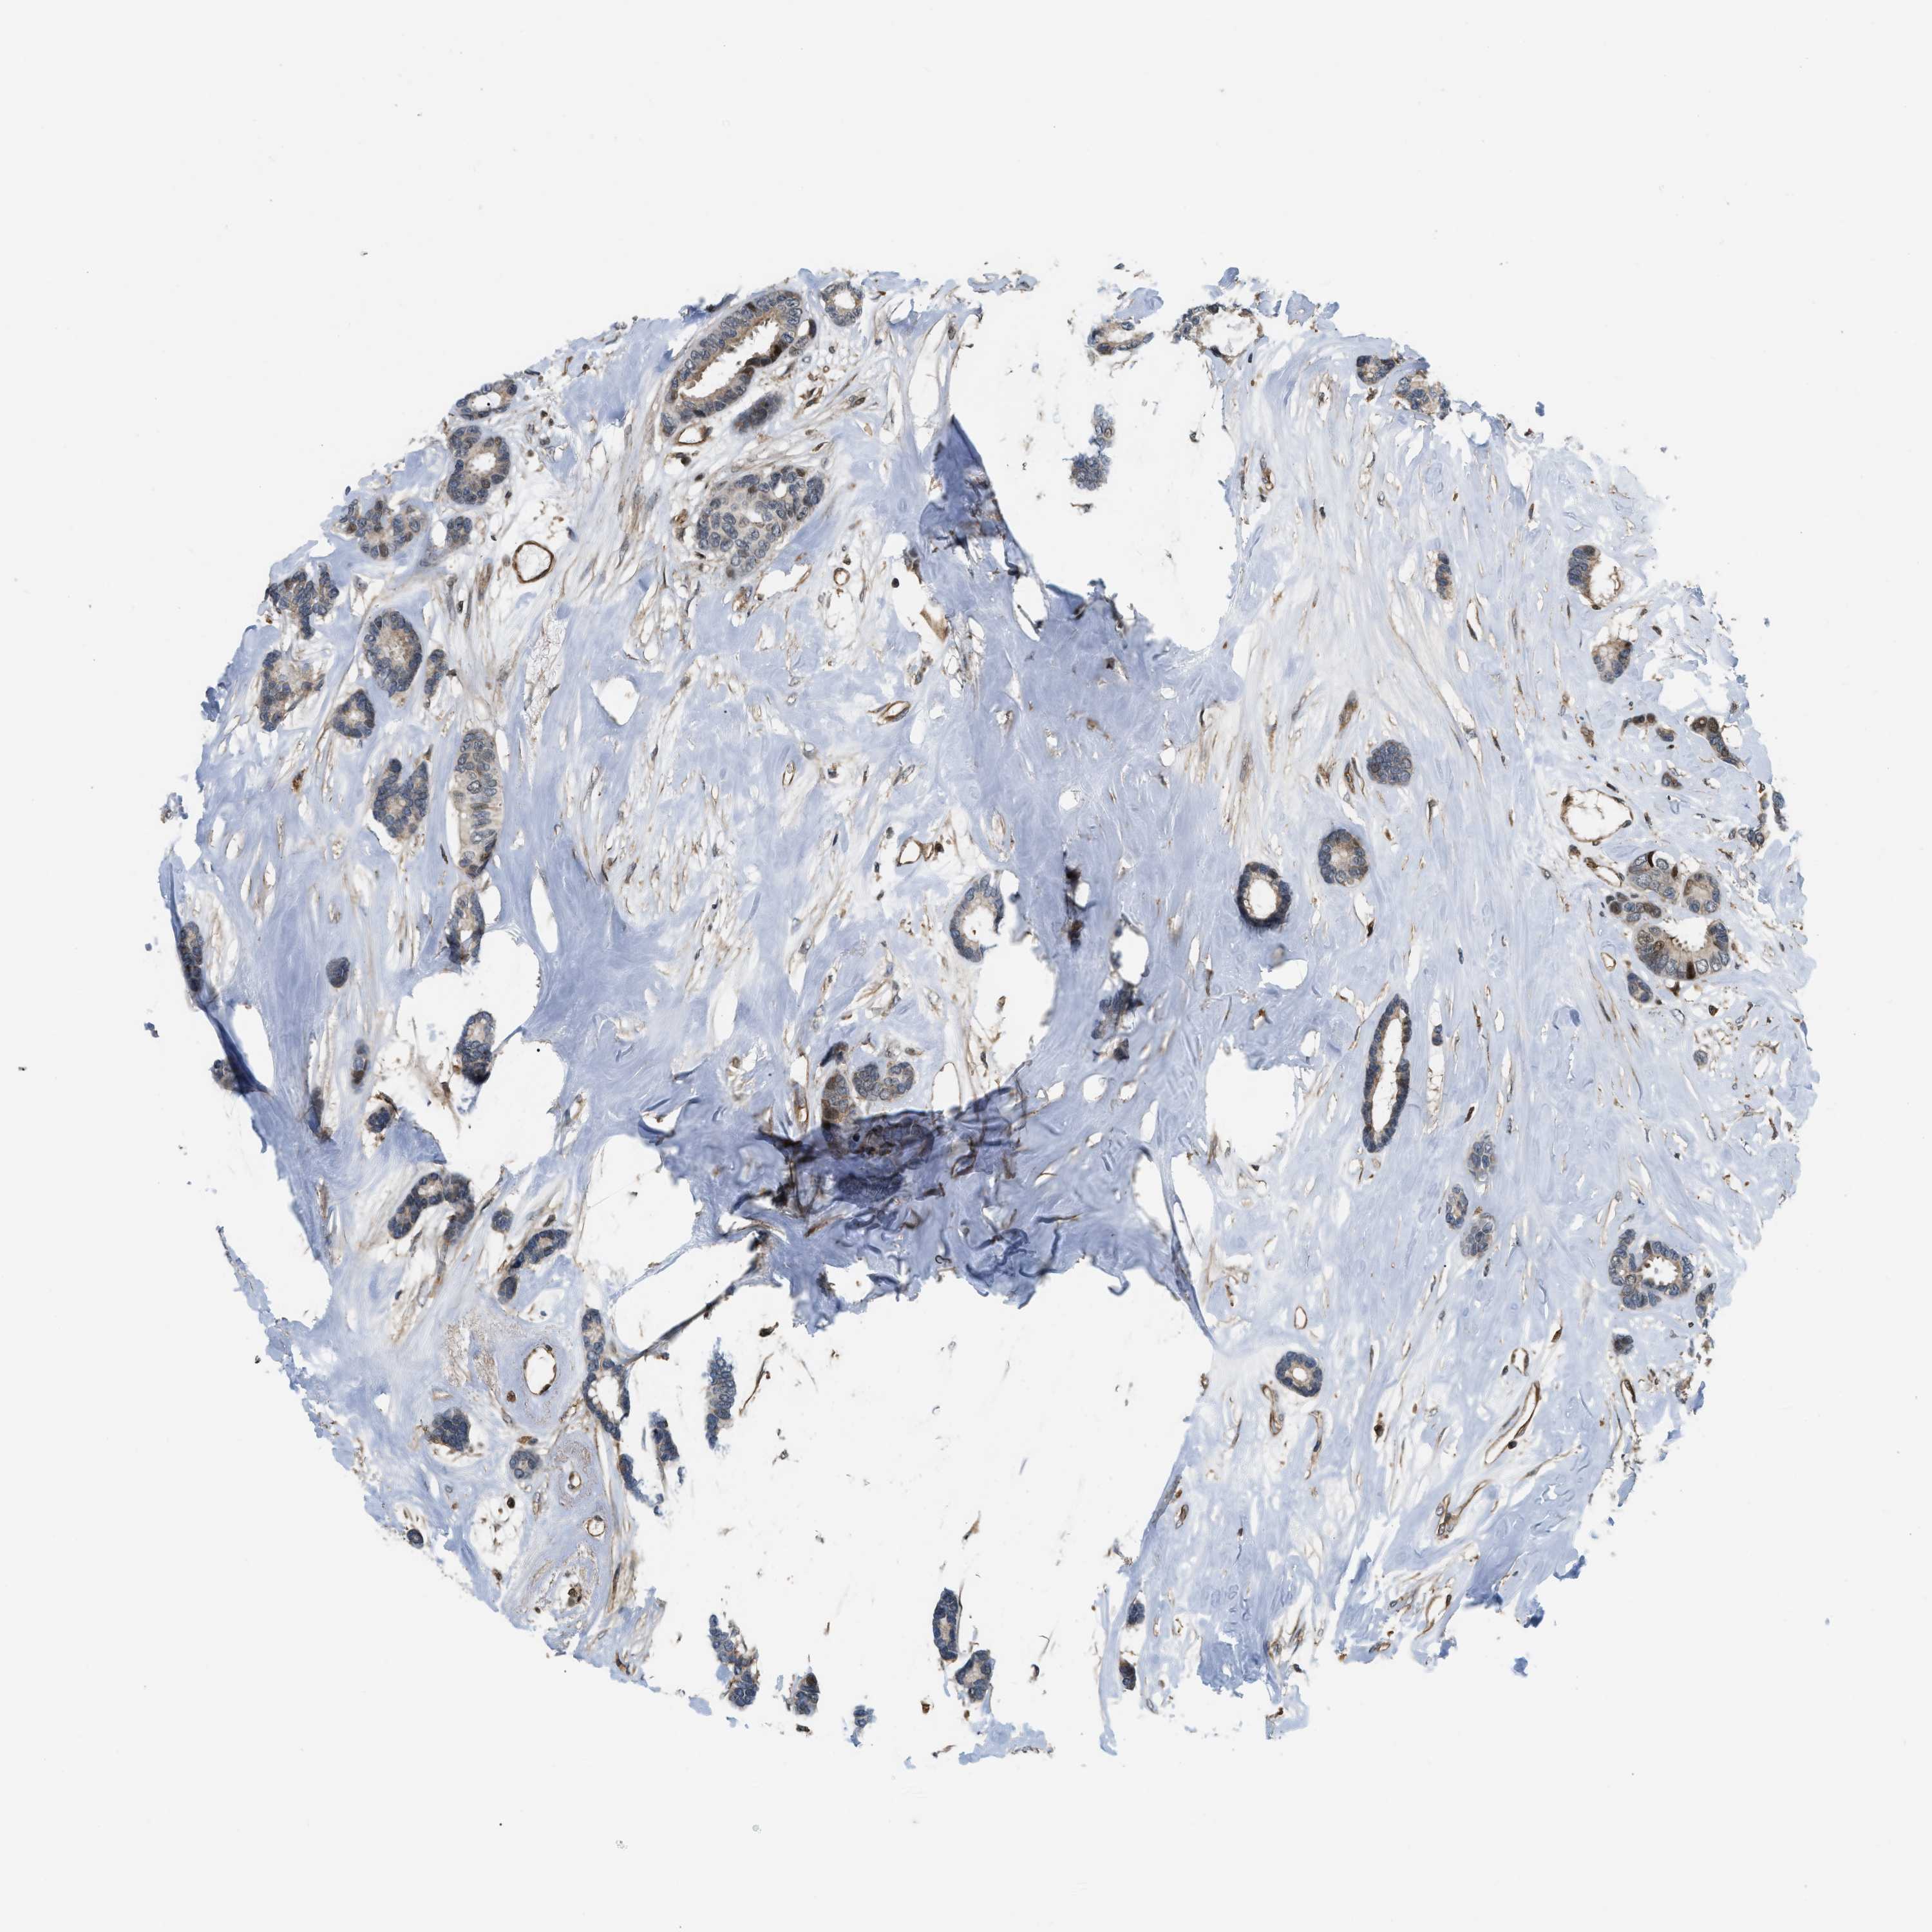

CANCER BREAST CANCER Show tissue menu

Breast cancer

Human cancer